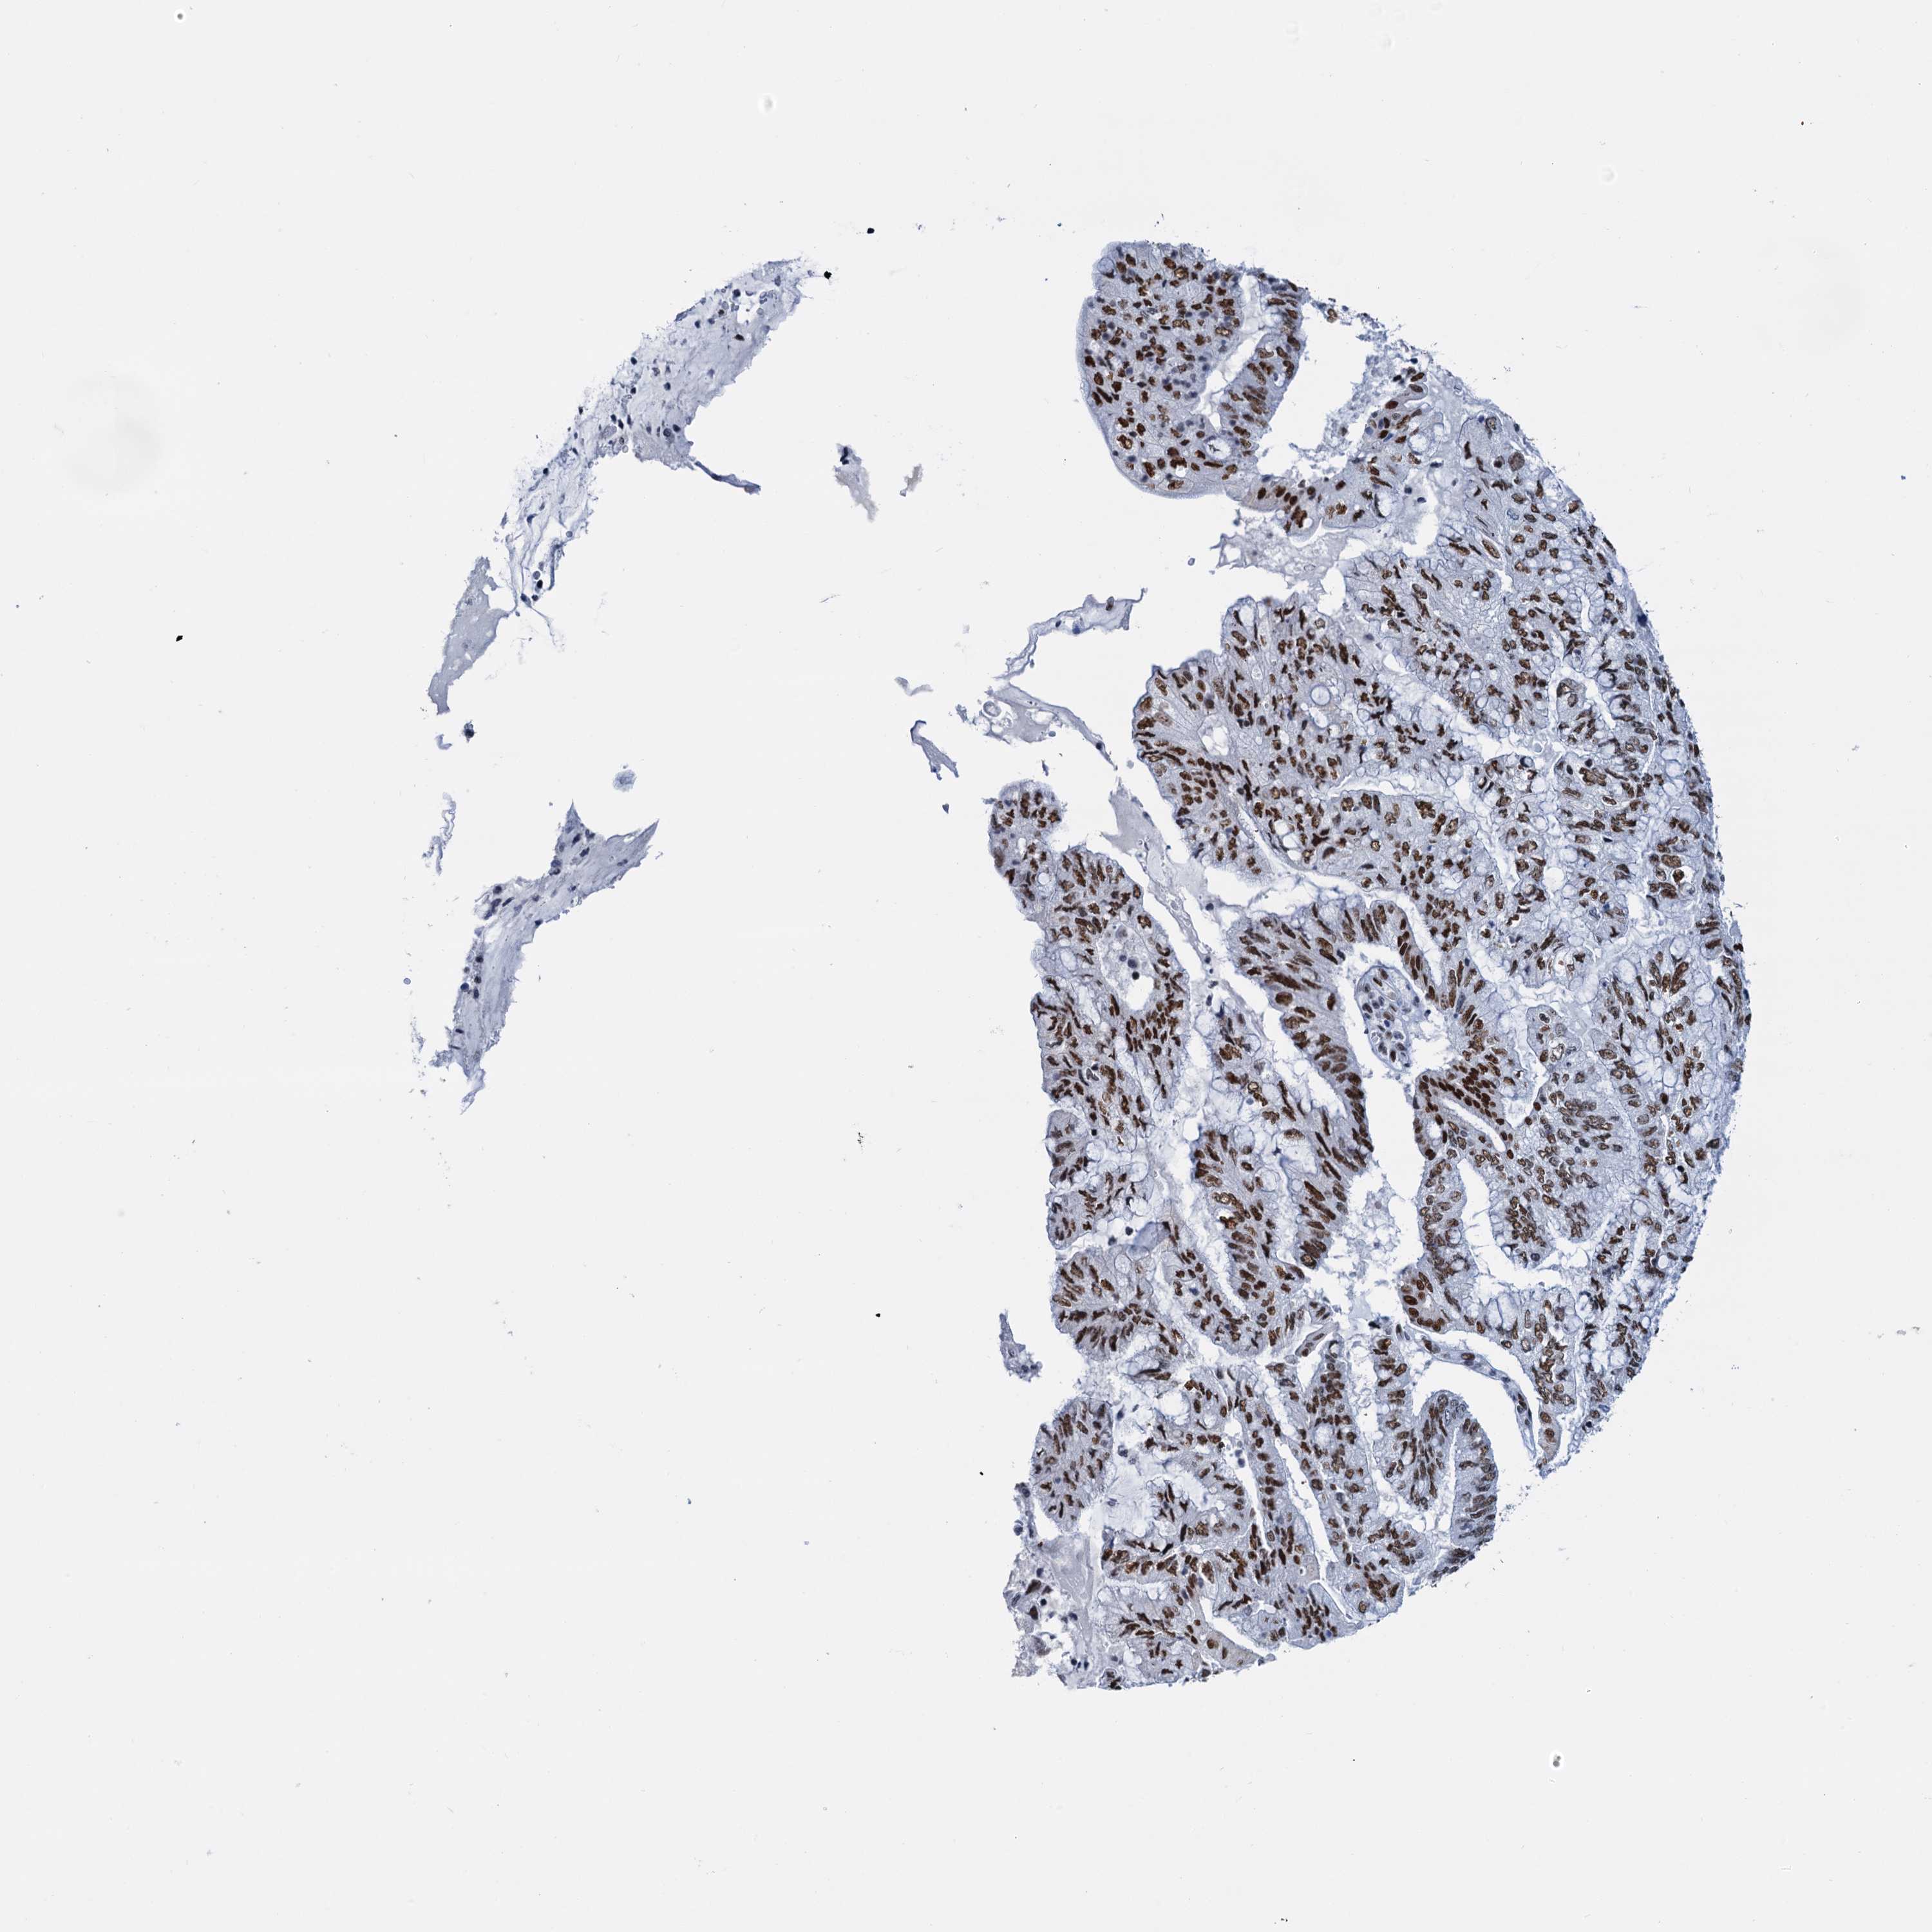

PANCREATIC CANCER - Protein expressioni

A mouse-over function shows sample information and annotation data. Click on an image to view it in a full screen mode. Samples can be filtered based on level of antibody staining by selecting one or several of the following categories: high, medium, low and not detected. The assay and annotation is described here.

Note that samples used for immunohistochemistry by the Human Protein Atlas do not correspond to samples in the TCGA dataset.

Antibody stainingi

Antibody staining in the annotated cell types in the current human tissue is reported as not detected, low, medium, or high, based on conventional immunohistochemistry profiling in selected tissues. This score is based on the combination of the staining intensity and fraction of stained cells.

Each image is clickable and will lead to virtual microscopy that enables deeper exploration of all samples and also displays staining intensity scores, fraction scores and subcellular localization as well as patient and tissue information for each sample.

Antibody HPA040256

Antibody HPA040381

Staining

High

Medium

Low

Not detected

Intensity

Strong

Moderate

Weak

Negative

Quantity

>75%

75%-25%

<25%

None

Location

Nuclear

Cytoplasmic/membranous

Cytoplasmic/membranous,nuclear

Adenocarcinoma, NOS